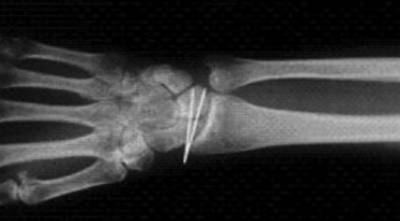

Ecart entre le scaphoïde et le semi-lunaire

Des radiographies simples du poignet seront toujours demandées. On recherchera des fractures associées et des écarts anormaux entre les différents os du carpe.

Fixation temporaire des broches

Dans les autres cas, il faudra envisager un traitement chirurgical ambulatoire (vous entrez et sortez de l’hôpital le même jour que votre intervention) sous anesthésie loco-régionale (seul le bras est endormi) afin de réparer le ligament abîmé. Le principe du traitement est de remplacer le ligament abîmé par une autre structure (ligamentoplastie ou capsulodèse) et de remettre en place les 2 os qui étaient maintenus par le ligament abîmé en les fixant temporairement par des broches qui seront laissées en place environ 8 semaines.